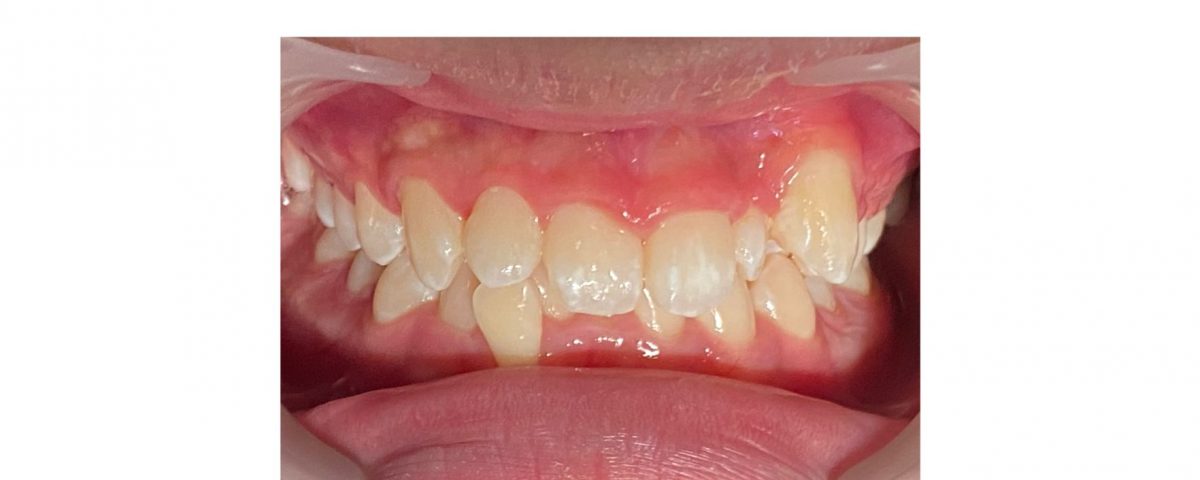

A 14 years old boy presented to our clinic with severe class I malocclusion. His upper left canine is completely squeezed out of the dental arch, upper left central incisor and lateral incisor are rotated. Lower dental arch is narrow and also having severe crowding on lower incisors. Lower right lateral incisor is displaced completely out from the dental arch.